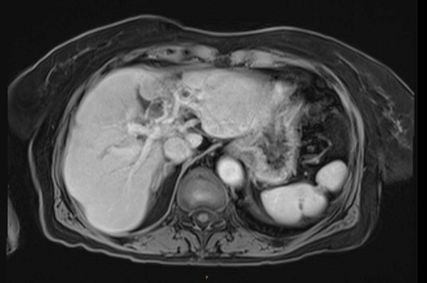

Die initiale CT zeigte eine bis zu 6cm große Raumforderung, ausgehend von der Hepatikusgabel, mit zentraler Infiltration des Leberparenchyms, suspekten Lymphknoten im Leberhilus und retroperitoneal, deutlich dilatierten intrahepatischen Gallengängen sowie Umscheidung und Infiltration des linken Pfortaderastes, jedoch ohne Thrombose. Der Befund war hochverdächtig auf einen cholangiozellulären Tumor. Die histologische Aufarbeitung einer Punktionsbiopsie ergab jedoch ein gering differenziertes, hiläres hepatozelluläres Karzinom (WHO 2019: G3). Angesichts des bildgebenden Befundes und des ebenfalls erhöhten Ca19-9 stand der Verdacht auf einen Mischtumor im Raum.

In der durchgeführten Staging-CT zeigte sich ein partielles Ansprechen (PR) mit Tumorgrößenreduktion von 49mm auf 33mm, die Lymphknoten blieben unverändert. Die Tumormarker sanken (AFP: 150, Ca19-9: 65). Aufgrund der persistierenden Diarrhö und des Verdachts auf einen Mischtumor erfolgte eine Umstellung der Therapie auf Cisplatin/Gemcitabin/Bevacizumab, wobei Gemcitabin ab Zyklus 2 wegen Fatigue auf 75% reduziert wurde und Cisplatin ab Zyklus 3 aufgrund von Ototoxizität abgesetzt werden musste. Nach vier Zyklen zeigte die MRT ein weiteres partielles Ansprechen (19×21mm), die Lymphknoten waren unverändert, die Tumormarker normalisierten sich erstmals.

Bildgebend können sich Mischtumoren wie ein HCC-iCCA-Gemisch imponierend darstellen, wie ein typisches HCC oder aber ein typisches iCCA aussehen oder sich unspezifisch darstellen. Bildgebende Hinweise auf Mischtumoren bestehen bei verschiedenartigem Kontrastmittelverhalten innerhalb eines Tumors (im Verlauf zunehmende Anreicherung, Anreicherung mit Wash-out, Anreicherung ohne Wash-out oder Hypovaskularisierung), vaskulärer Invasion und Gallengangsbeziehungen. Die Kombination erhöhter Tumormarker (AFP und Ca19-9) kann einen Hinweis liefern, ist aber nicht beweisend.